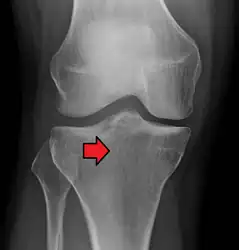

Lipohemarthrosis (presence of fat and blood from bone marrow in the joint space after an intraarticular fracture) seen on X-ray in a person with a subtle tibial plateau fracture

Lipohemarthrosis due to a tibial plateau fracture